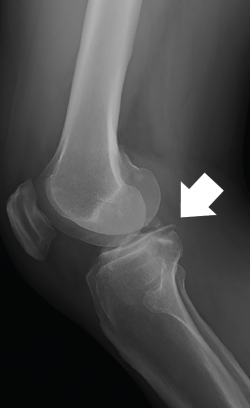

En el estudio mediante tomografía computarizada (TC) se identificó una fractura de la región posterior del platillo tibial interno con hundimiento milimétrico y fragmentos avulsionados infracentimétricos colocados inmediatamente mediales al ligamento cruzado posterior (LCP) juntamente con una pequeña fractura en la cortical posterior del platillo tibial externo sin hundimiento, desplazamiento ni conminución (Figura 2).

Figura 2. En las imágenes en axial (A), sagital (B) y coronal (C) de la tomografía computarizada se observan los fragmentos óseos avulsionados dependientes de la raíz posterior del menisco medial cerca de la inserción del ligamento cruzado posterior.